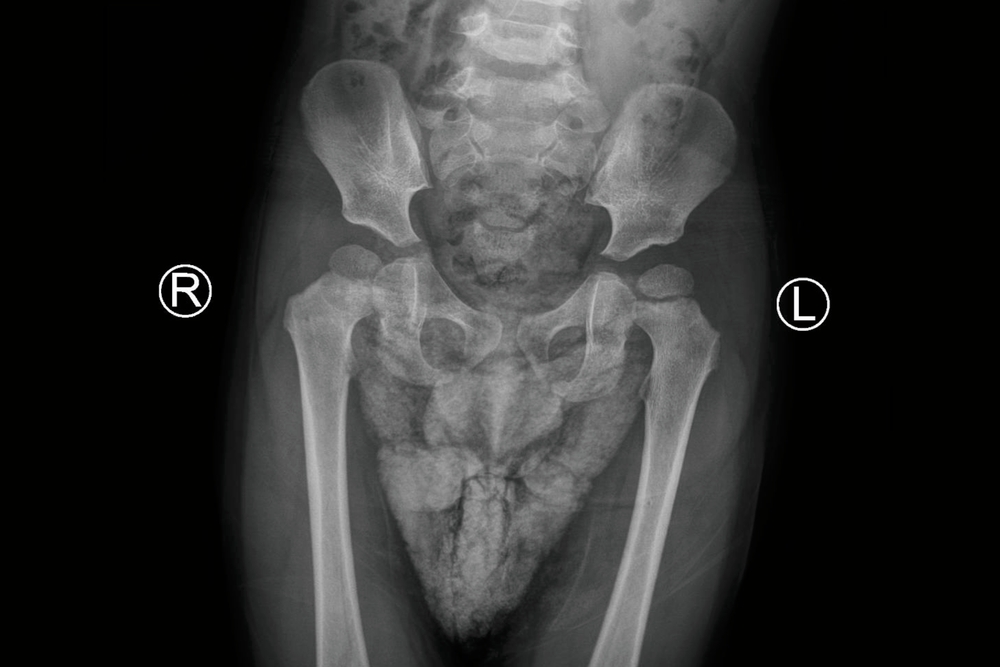

Πόνος στο ισχίο

Ο πόνος στο ισχίο είναι ένα σύμπτωμα που μπορεί να οφείλεται σε πληθώρα διαφορετικών παθολογικών καταστάσεων. Αποτελεί έναν από τους συχνότερους λόγους επίσκεψης στον ορθοπαιδικό, ιδιαίτερα σε άτομα μέσης και μεγαλύτερης ηλικίας. Η εντόπισή του δεν περιορίζεται απαραίτητα στην ίδια την άρθρωση, η οποία βρίσκεται …